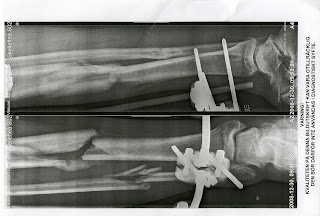

Röntgen bilder från den 30/12 när man ser dom kan man

inte tro att det hände i september har inte läkt så bra.

Höger underben